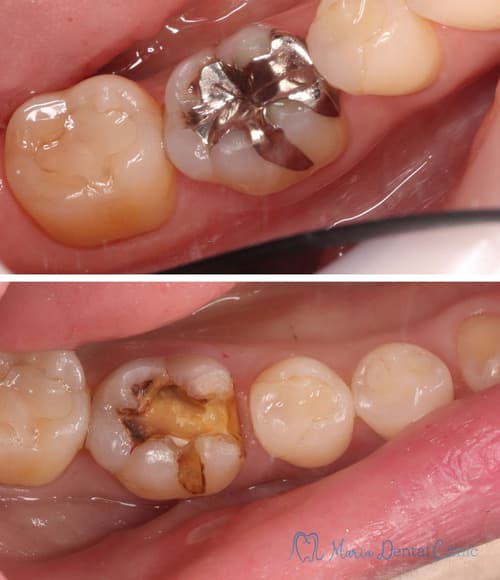

中等度の虫歯

虫歯を完全に除去した後に辺縁隆線の喪失や咬頭の歯質の厚みが菲薄(ひはく)化することで、歯の厚みが十分でなくなった場合は、歯の形態の回復と強度を維持するために、型取りを行い歯冠修復を行う必要がある。

歯冠修復の種類には、インレー、アンレー、クラウンの代表的な3つがあります※3。

虫歯を徹底的に予防できる素材としては、セラミックかゴールドが望ましいと考えられます。